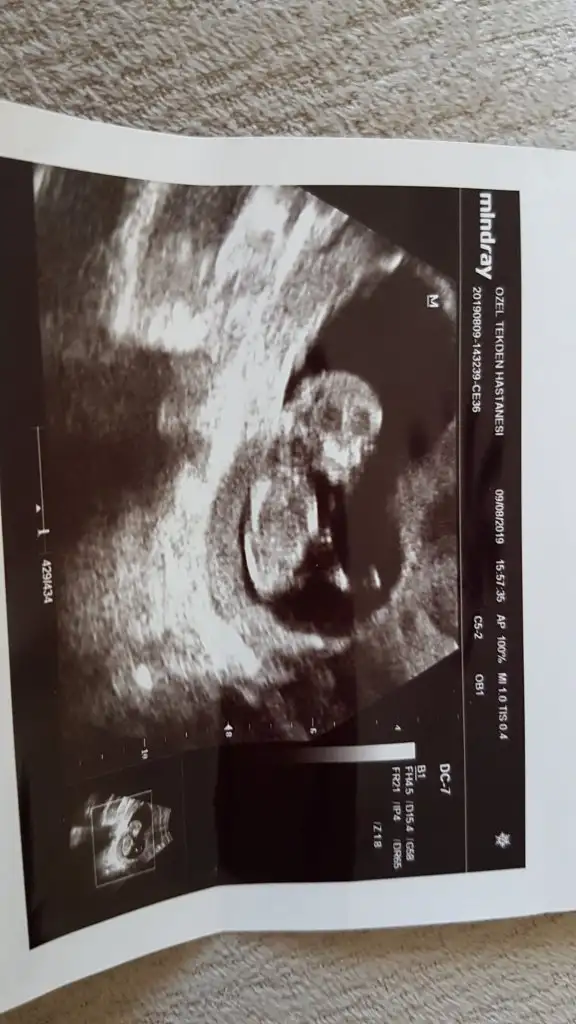

Merhaba ben de bir tahmin alabilir miyim. 11+4 haftalıkken.